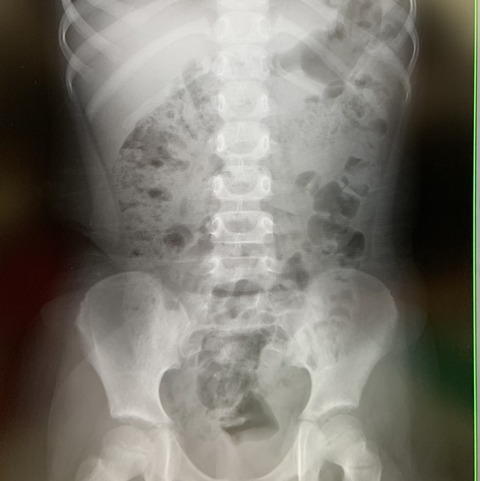

■血液検査

脱水関連で引っかかるも、他が問題ない(腎臓も肝臓もバッチリ)ので、気にしなくていいそうです

血小板が少ないと値で出ていますが、先生が血液を顕微鏡でしっかり見て問題ないことを確認したそうなので、こちらも大丈夫とのこと

■体重

3.86キロ

太ってもやせてもなく、標準とのこと。

■便検査

異常なし